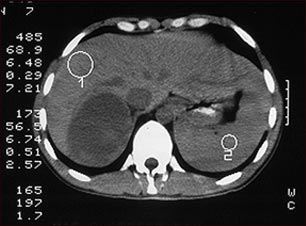

Tumor suprarrenal, tomografía computarizada

TC del abdomen superior de una persona con una masa en la glándula suprarrenal derecha. Las glándulas suprarrenales están situadas por encima de los riñones.